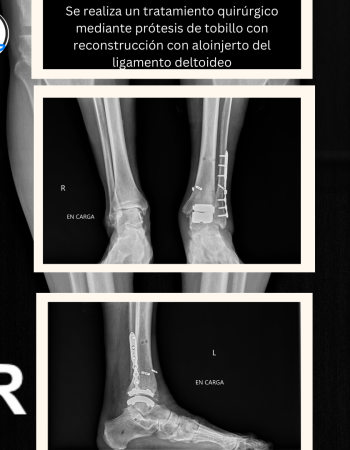

En la radiografías en carga se aprecia una artrosis asimétrica con el tobillo en valgo, muy probablemente debido a una inestabilidad medial por lesión del ligamento deltoideo.